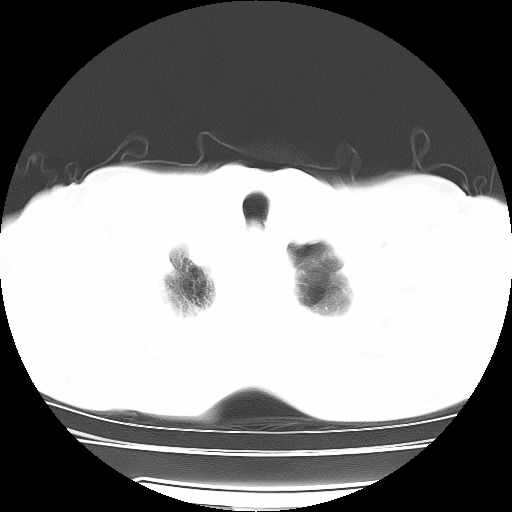

男,71岁,咳嗽,气喘10年,再发并咯血.胸片见气胸

考虑  左肺中心型肺癌伴阻塞性肺炎,肺不张,纵膈淋巴结肿大。慢支炎,肺气肿,左侧气胸肺压缩5%

左侧中央型肺癌伴纵膈淋巴结转移。

左肺中心型肺癌伴阻塞性肺炎,肺不张,纵膈淋巴结肿大

1)考虑左肺中心型肺癌伴阻塞性肺炎、左肺下叶肺不张、左侧肺气肿,纵膈淋巴结转移。2)左侧气胸(肺组织压缩约5%)。

左肺中心型肺癌伴阻塞性肺不张、肺气肿 。

1)考虑左肺中心型肺癌伴阻塞性肺炎、左肺下叶肺不张、左侧肺气肿,纵膈淋巴结转移。2)左侧气胸。